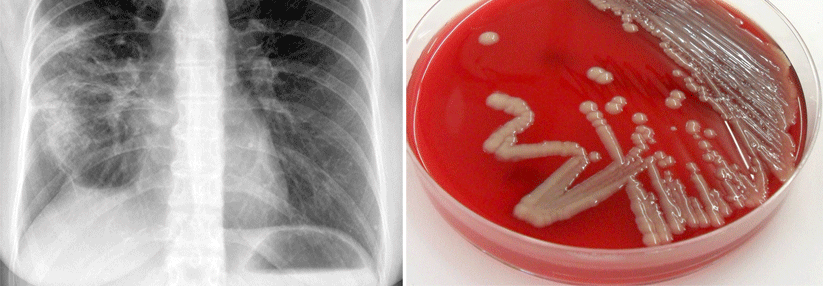

Ist die Pneumonie für Sie ein Kinderspiel?

Wenn Kinder mit Fieber, Husten und Dyspnoe in der Praxis vorgestellt werden, fällt der Verdacht schnell auf eine Pneumonie. Dann stellt sich die Frage, ob der kleine Patient ins Krankenhaus muss oder noch zu Hause behandelt werden kann und natürlich mit welcher Therapie.

Von einer ambulant erworbenen Pneumonie spricht man, wenn die Symptome außerhalb des Krankenhauses beginnen oder innerhalb von 48 Stunden nach stationärer Aufnahme. Kinder mit pCAP (paediatric community-acquired pneumonia) präsentieren sich typischerweise mit Fieber, Tachypnoe, Dyspnoe und Husten sowie einem reduzierten Allgemeinzustand. Hinzu kommen häufig Thorax- und Bauchschmerzen sowie Erbrechen. Auch Nahrungsverweigerung, Inaktivität und veränderte Vigilanz (Apathie, Agitiertheit) können auf eine pCAP hinweisen. Die höchste Sensitivität und Spezifität haben Studien zufolge Fieber und Tachy­pnoe. Allerdings ist dabei zu beachten, dass manche Patienten nur Fieber entwickeln – ohne…